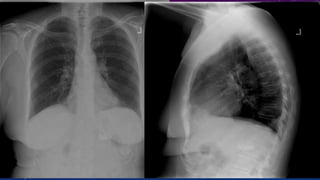

MULTIPLE GALL STONES

GB AND RIGHT RENAL CALCULI.

CHRONIC CALCIFIC PANCREATITIS